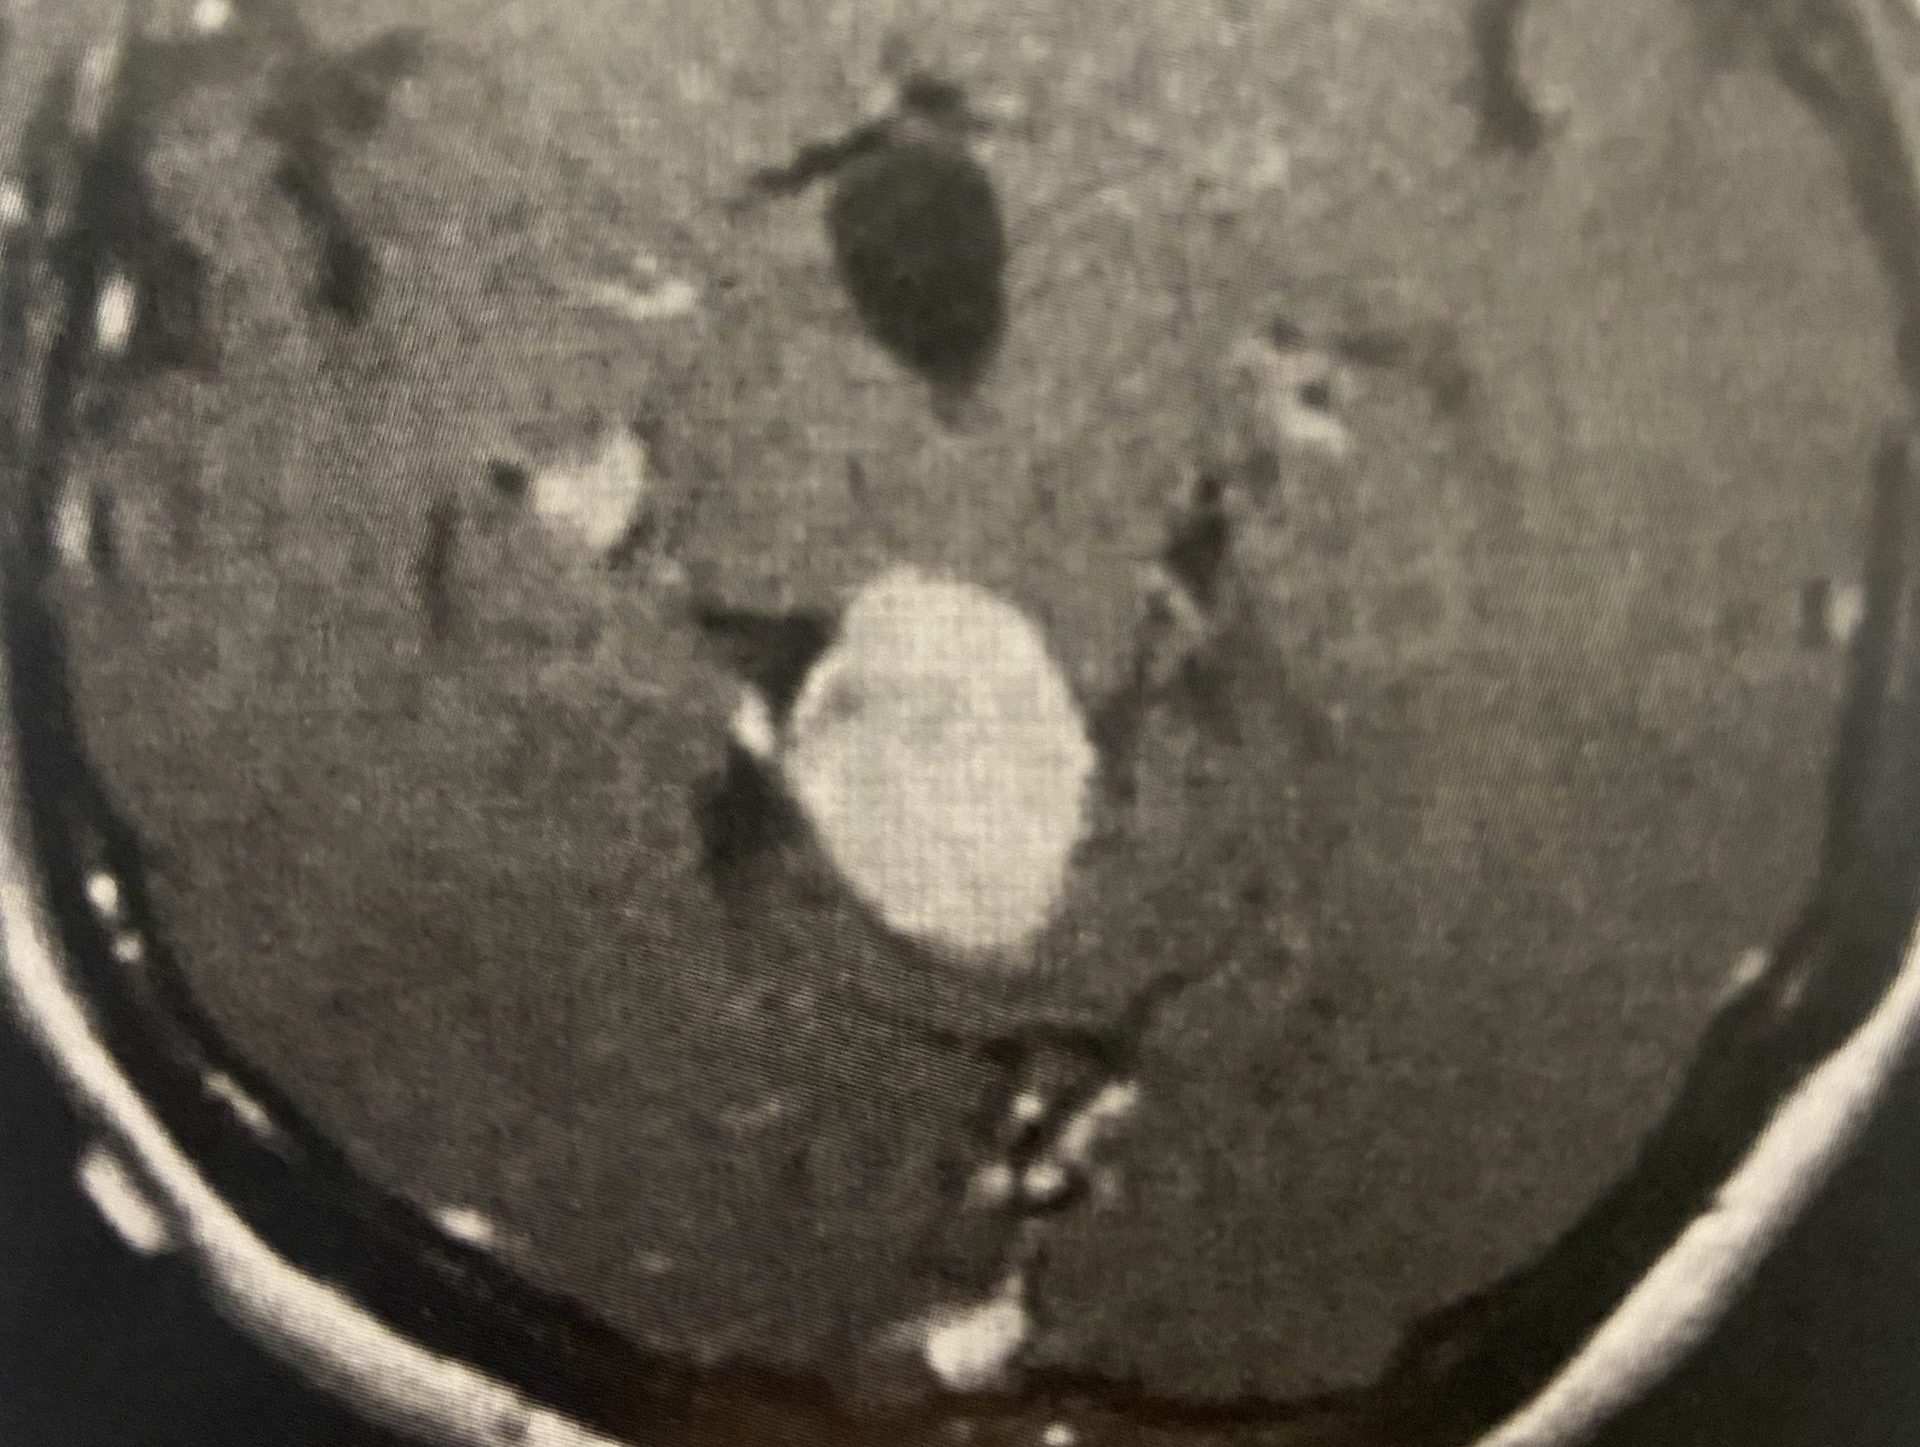

(Fig. 3) AP and Lateral cervical X-ray 6 months from surgery demonstrates a stable construct and alignment.

Postoperatively the patient had an uneventful course with relief of her right arm pain and stable construct (Fig. 3) at follow up at 6 months.